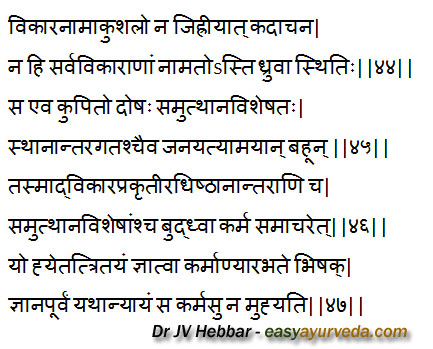

Correct approach to the diagnosis and treatment

If a physician is not able to name a particular disease, he should not feel ashamed on that account because it is not always possible to name all types of diseases in definite terms. When aggravated, a single Dosha may cause manifold diseases depending upon the various etiological factors and the sites of manifestation.

So a physician should try to comprehend the nature of the disease based on Dosha, the site of its manifestation and etiological factors and should then initiate the treatment, A physician who so initiates the treatment after having full knowledge of the therapeutic properties of these three aspects and paying due regard to scriptural instructions would never fail in his attempt to cure the disease.[44-47]